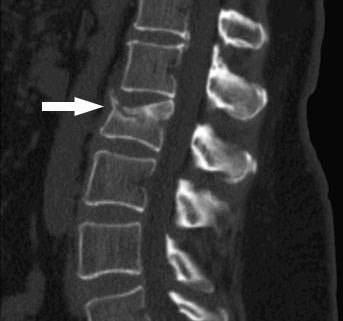

Другие обследования, которые могут измерить плотность костной ткани:

- Компьютерная томография (КТ)